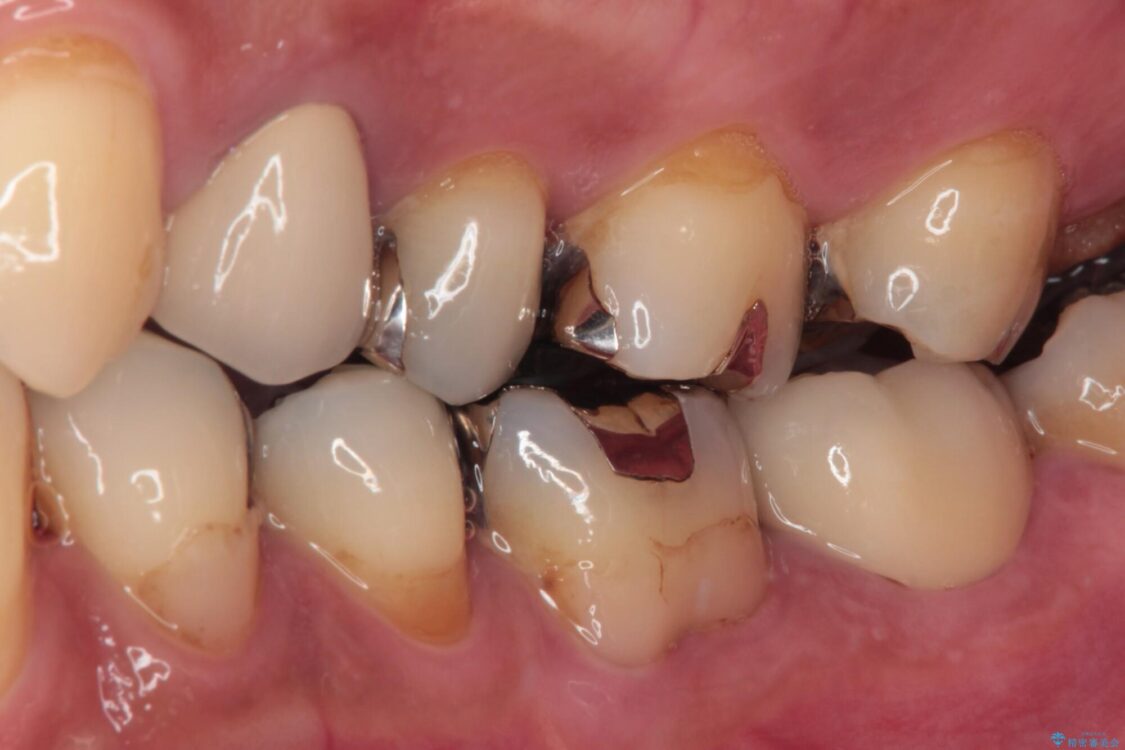

歯質の欠損が大きいため、処置後はオールセラミッククラウンにて補綴治療を行うこととしました。

治療後

• 治療をしても違和感の続く奥歯 神経を極力残した虫歯治療 治療後画像